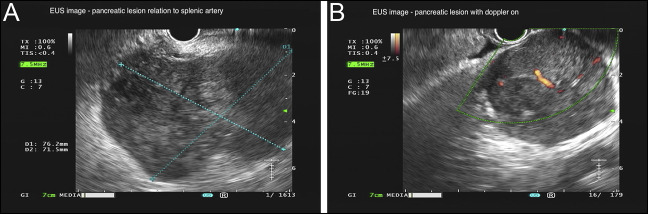

外阴黑色素瘤(VM)是一种罕见的侵袭性恶性肿瘤,具有很高的转移潜力。我们提出一个82岁的妇女谁最初提出阴道出血,并被诊断为VM与淋巴结累及的情况下。尽管进行了手术和姑息治疗,她后来还是出现了脑、淋巴结和胰腺转移。内镜超声引导下细针活检(EUS-FNB)经免疫组化证实胰腺转移。据我们所知,这是第一例用EUS-FNB诊断的VM胰腺转移病例。本病例强调了EUS-FNB在诊断异常部位转移性病变中的重要性。

Vulvar melanoma (VM) is a rare and aggressive malignancy with a high metastatic potential. We present the case of an 82-year-old woman who initially presented with vaginal bleeding and was diagnosed with VM with lymph node involvement. Despite surgical and palliative interventions, she later developed brain, nodal, and pancreatic metastases. Endoscopic ultrasound-guided fine-needle biopsy (EUS-FNB) confirmed pancreatic metastasis through immunohistochemistry. To our knowledge, this is the first reported case of pancreatic metastasis from VM diagnosed by EUS-FNB. This case highlights the importance of EUS-FNB in diagnosing metastatic lesions in unusual locations.